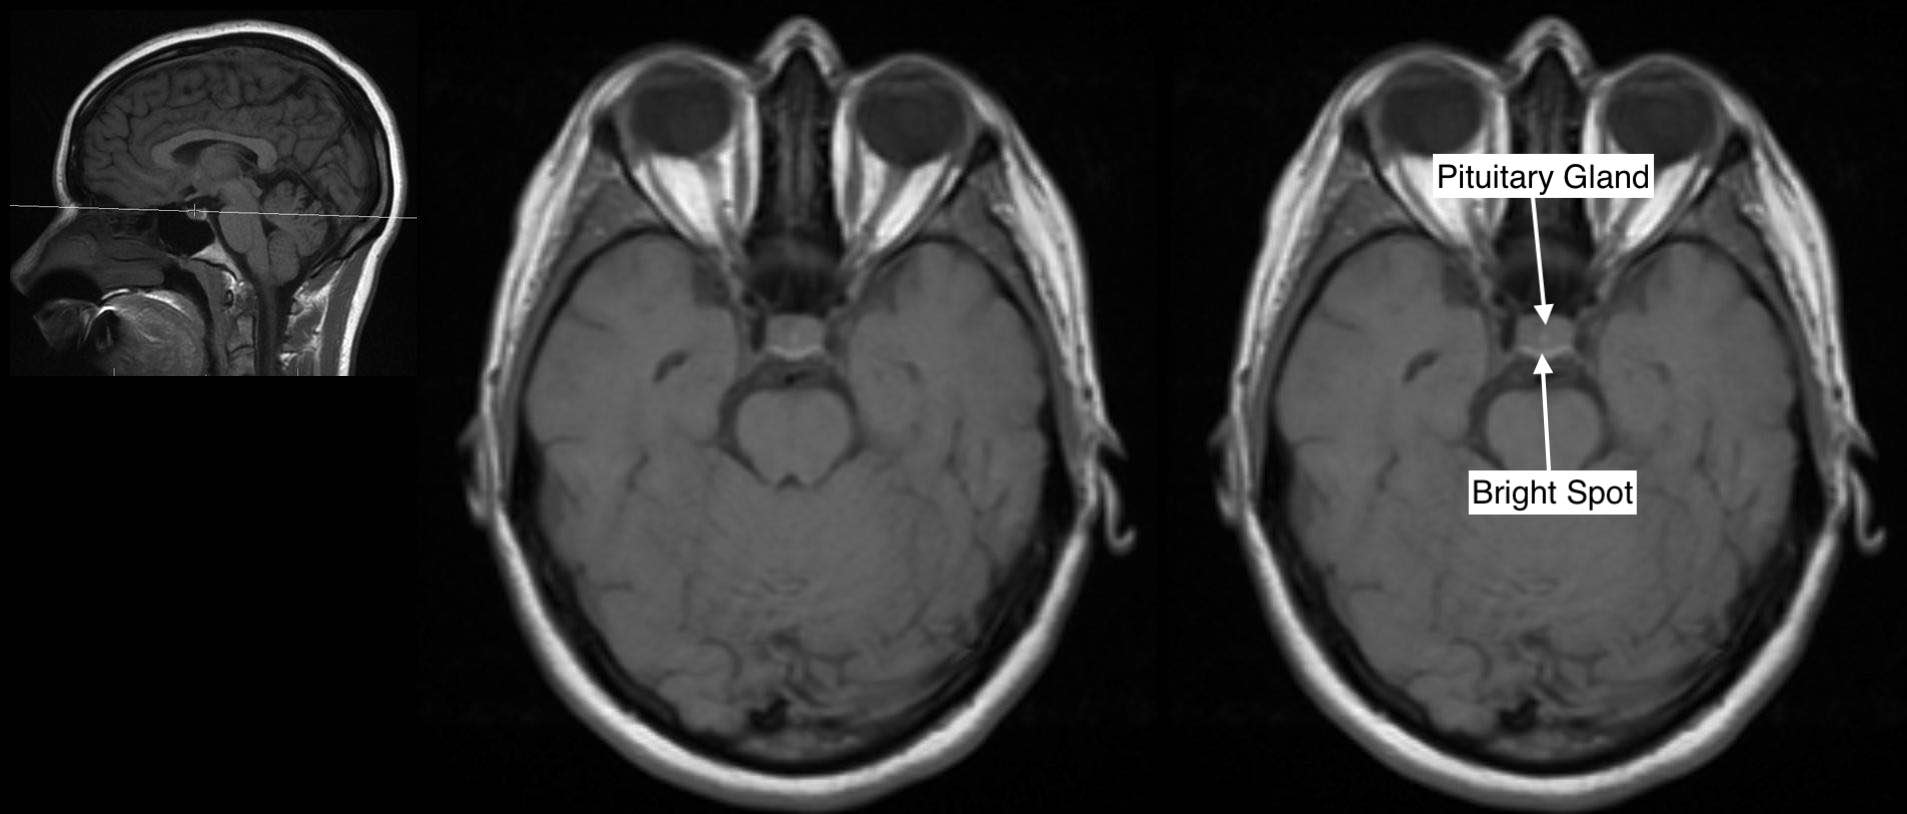

MRI Studies of the Patient's Pituitary Gland MRI of the pituitary gland... Download Scientific What Is A Mri Of The Pituitary Gland a pituitary mri (magnetic resonance imaging) is an imaging test that makes pictures of the pituitary gland (small gland. a magnetic resonance imaging scan, also called an mri scan, is a test that uses a magnetic field and computer. learn about pituitary tumors, also called pituitary adenomas, which are noncancerous growths in the pituitary. the initial. What Is A Mri Of The Pituitary Gland.

Head, brain and pituitary gland, MRI scan Stock Image C037/3115 Science Photo Library What Is A Mri Of The Pituitary Gland the initial recommended diagnostic test for pituitary lesions is a specialized mri pituitary protocol, both with and without intravenous. a magnetic resonance imaging scan, also called an mri scan, is a test that uses a magnetic field and computer. learn about pituitary tumors, also called pituitary adenomas, which are noncancerous growths in the pituitary. a pituitary. What Is A Mri Of The Pituitary Gland.